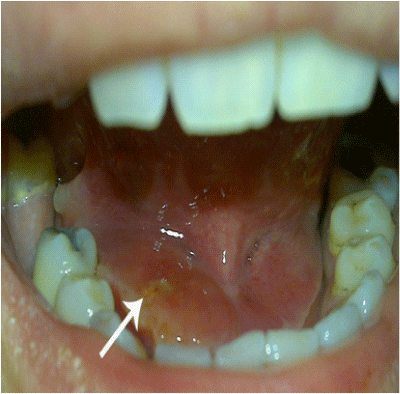

On day one of admission, she passed the stone out without any surgical intervention, leaving a dilated opening of the Wharton’s duct in the floor of mouth (Figure 3). The stone was yellow, firm with relatively smooth surface. The stone was 17 X 4 X 3 mm and was “olive-pit” shaped, almost fitting the shape of the duct (Figure 4). This appearance is similar to the normal ductal sialoliths in patients with submandibular gland. Since the stone had passed, she clinically improved and was later discharged home.

Figure 3 Photo of the patient’s floor of mouth showing the dilated opening of the Wharton’s duct after the stone had passed.